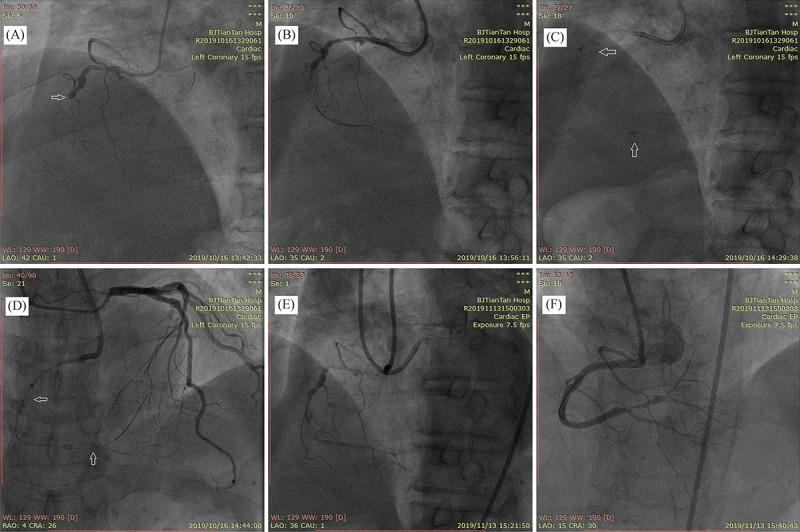

Subintimal plaque modification (SPM) is often performed to restore antegrade flow and facilitate subsequent lesion recanalization. This study aimed to compare the safety and efficacy of modified SPM with traditional SPM.

A total of 1454 consecutive patients who failed a chronic total occlusion percutaneous coronary intervention (CTO PCI) attempt and underwent SPM from January 2015 to December 2019 at our hospital were reviewed retrospectively. Fifty-four patients who underwent SPM finally were included in this study. We analyzed the outcomes of all the patients, and the primary endpoint was recanalization rate, which was defined as Thrombolysis in Myocardial Infarction (TIMI) grades 2-3 flow on angiography 30 to 90 days post-procedure.

The baseline characteristics were similar between the two groups. In the follow-up, the recanalization rate was noticeably higher in the modified SPM group compared with the traditional SPM group (90.9% 62.5%, < 0.05). The proposed strategy in the modified group was more aggressive, including a larger balloon size (1.83 ± 0.30 2.48 ± 0.26 mm, < 0.05) and longer subintimal angioplasty (0.59 ± 0.16 0.92 ± 0.12 mm, < 0.05). Also, the common use of a Stingray balloon and guide catheter extension resulted in improvement of patients in the modified SMP group (12.5% 100%, < 0.05).

Modified SPM, which is associated with a high likelihood of successful recanalization, is an effective and safe CTO PCI bail out strategy.